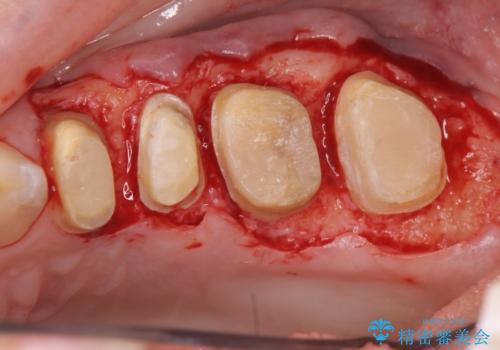

放置してしまった深い虫歯の治療

- 虫歯治療を中断し放置、痛みが出てきたため当院を初診来院されました。

虫歯の深化により根管治療、歯周外科手術を行い歯肉の状態を改善し精密なセラミッククラウンを製作する治療を計画します。

セラミック治療の長期的な予後を見込むために、根管治療、歯周外科を行いクラウン装着前の環境を整えておくことが肝要です。